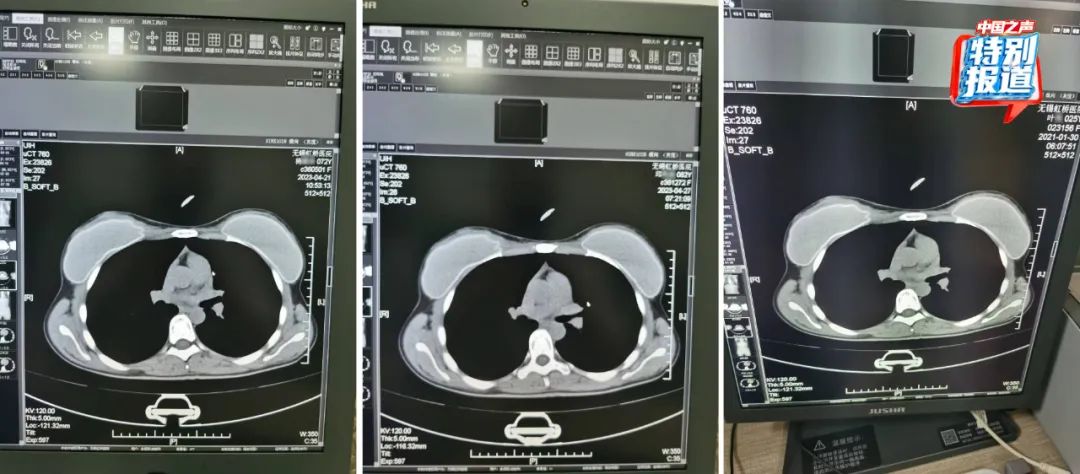

在被举报的病历中,杨某某(72岁)和邱某某(62岁)的病历里,有根据所拍片子的情况做出的诊断,却找不到对应的影像。6月份又查到了她们的CT影像,按照系统记录,这两人都是2023年4月做的胸部CT,片子上能清晰看出,两位患者的吊坠形状、大小和位置都基本一致。

不仅这两位上了年纪的患者CT影像类似,朱成刚比对发现,2021年在他们科做过CT的25岁女性叶某的片子上,也有看起来极为相似的吊坠,肉眼看,三人的片子几乎一模一样。

类似这样看上去雷同程度很高的片子,还有不少。系统显示:

患者李某某在2023年4月28日拍摄了胸部CT,她的影像与实际患者刘某在2024年2月的检查影像看起来高度相似。

74岁的患者莫某在2023年4月27日拍摄了胸部和颈椎的CT,她的片子看起来和实际患者37岁的马某某在2023年11月拍的片子高度相似,片子里能直观看到项链都一模一样。